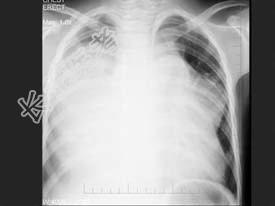

- 单项选择题男,13岁, 胸痛胸闷2月,胸部检查如图, 最可能的诊断为  (    )

A、心力衰竭并右侧胸腔积液

B、纵隔占位

C、先天性心脏病,房缺

D、先天性心脏病,动脉导管未闭

E、右侧胸腔大量积液